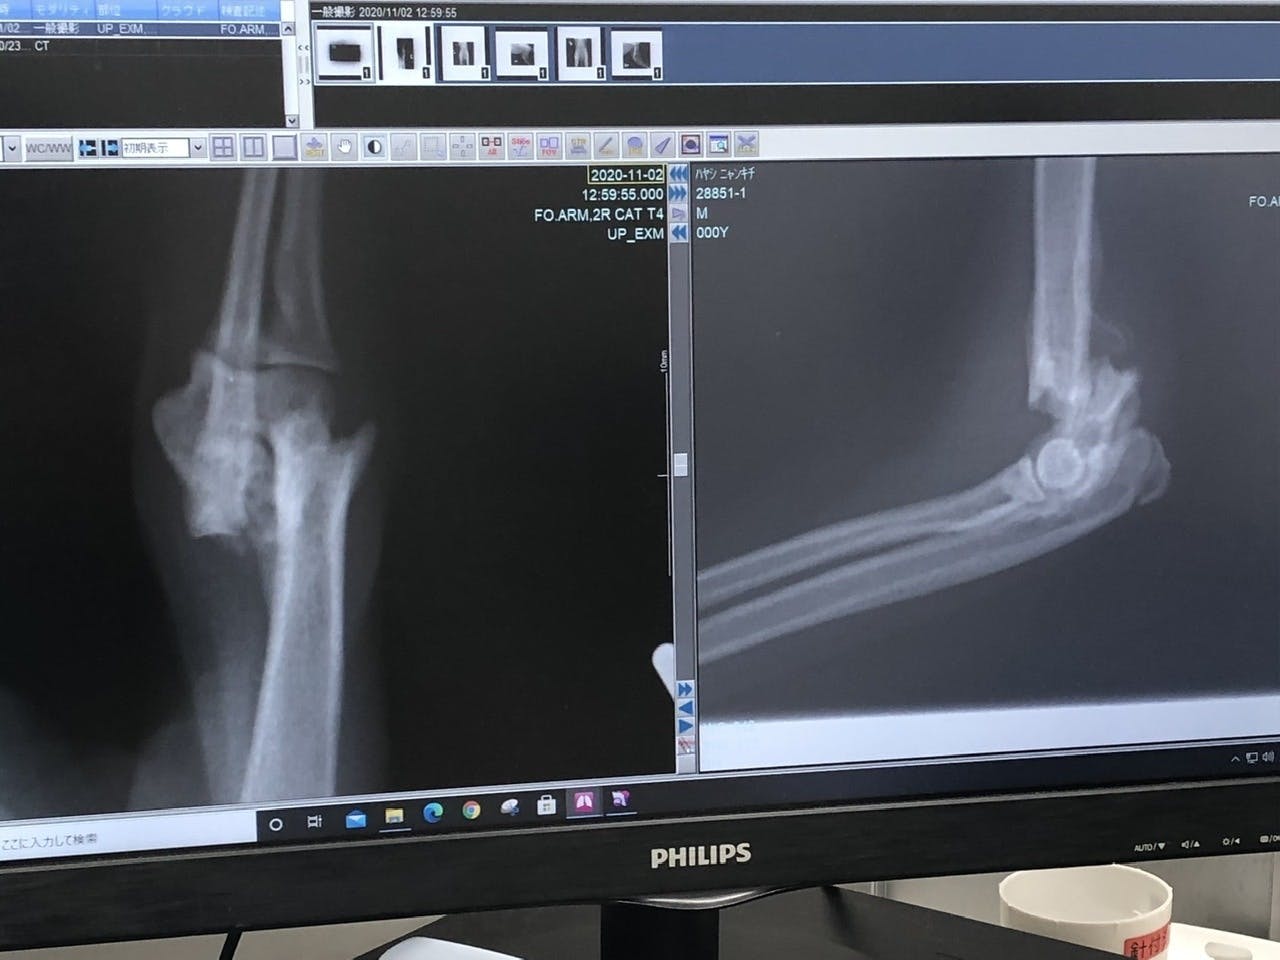

「右上腕部末端(肘)骨折」

それ以外のキズや臓器系、病気などは無く、強い衝撃が生後間もなく右半分に当たり、骨折したものだと、先生がおっしゃられていました。

再度診察の結果、「右上腕部末端(肘)」が、折れた骨の周辺の肉(繊維)が固まってきており、神経が多く通ってる箇所なんで、逆に傷つける恐れがあるとの事で、今回は見送られました。徐々にですが体重もかけれるのと、後ろが治れば負担も少なくなるとの見解です。